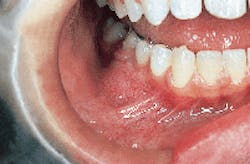

The patient`s vital signs were all found to be within normal limits. Examination of the head and neck region revealed no enlarged or palpable lymph nodes. Intraoral examination revealed a localized bony hard swelling buccal to teeth #28, 29, and 30 (see photo). The mass measured approximately 2.5 cm in diameter. Further examination of the oral tissues revealed no other lesions present.